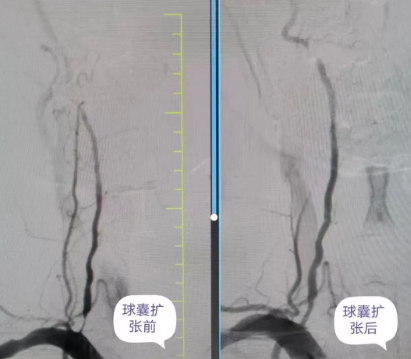

患者因長年累月的頭暈不適,前來國文醫(yī)院神經內科就診。經過頸動脈血管彩超和DSA的詳細檢查,確診為右側椎動脈起始段狹窄,狹窄程度高達86%。右側椎動脈作為腦部供血的重要通道,一旦閉塞,將引發(fā)嚴重的腦缺血,甚至威脅生命。因此,及時干預顯得尤為重要。

術中,丁金明主任、朱洪波副主任帶領團隊,通過導管精準地將球囊送至狹窄的椎動脈段,在確認球囊位置準確無誤后,仔細地進行擴張,直至狹窄的血管恢復到接近正常直徑。整個手術過程在專業(yè)團隊的精心操作下,僅30分鐘便順利完成。